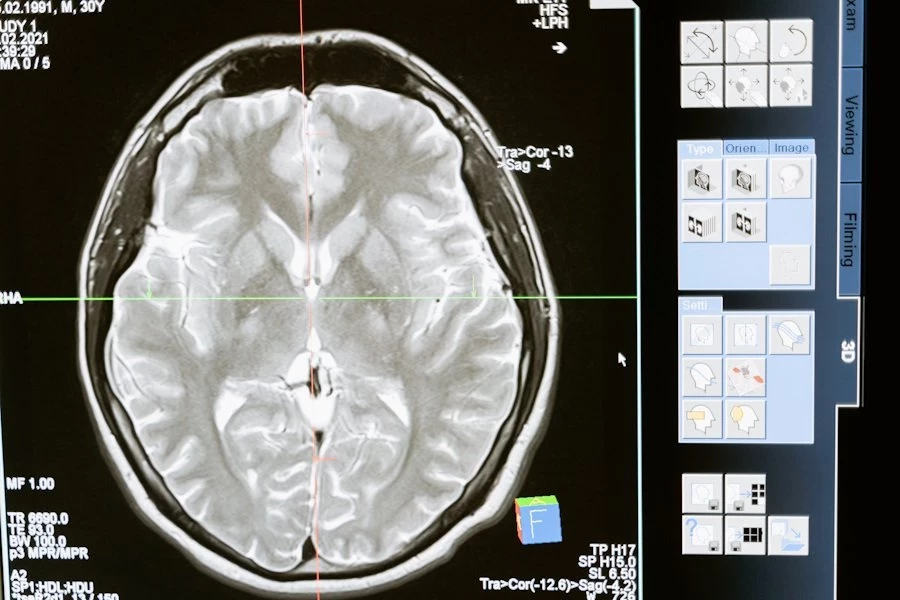

Precision Neuroscience, конкурент Neuralink, проводит клиническое исследование подключив свой нейроинтерфейс к мозгу человека

Precision утверждает, что их технология не потребует проведения открытой операции на головном мозге. В интервью с CNBC в январе соучредитель и генеральный директор компании Майкл Магер объяснил, что хирург сможет имплантировать устройство, сделав маленький разрез в черепе, который будет настолько тонким, что пациентам не придется брить волосы для процедуры.

Минимально инвазивный подход Precision является разумным выбором, поскольку другие конкурирующие компании, такие как Paradromics и Neuralink, разрабатывают системы, которые вводятся непосредственно в ткань мозга.

Рапопорт, представитель Precision, сказал, что введение интерфейса мозг-компьютер в мозг дает более детальное представление о работе каждого нейрона, но при этом может повредить ткань и сложно масштабироваться. Он отметил, что для достижения целей Precision, таких как распознавание речи и другие функции, не требуется такой высокий уровень детализации, поэтому компания согласилась на компромисс.

В ближайшие недели Precision планирует провести процедуру с двумя пациентами в рамках клинического исследования. Они также надеются опубликовать свои первоначальные результаты в научном журнале, что будет огромным шагом вперед.